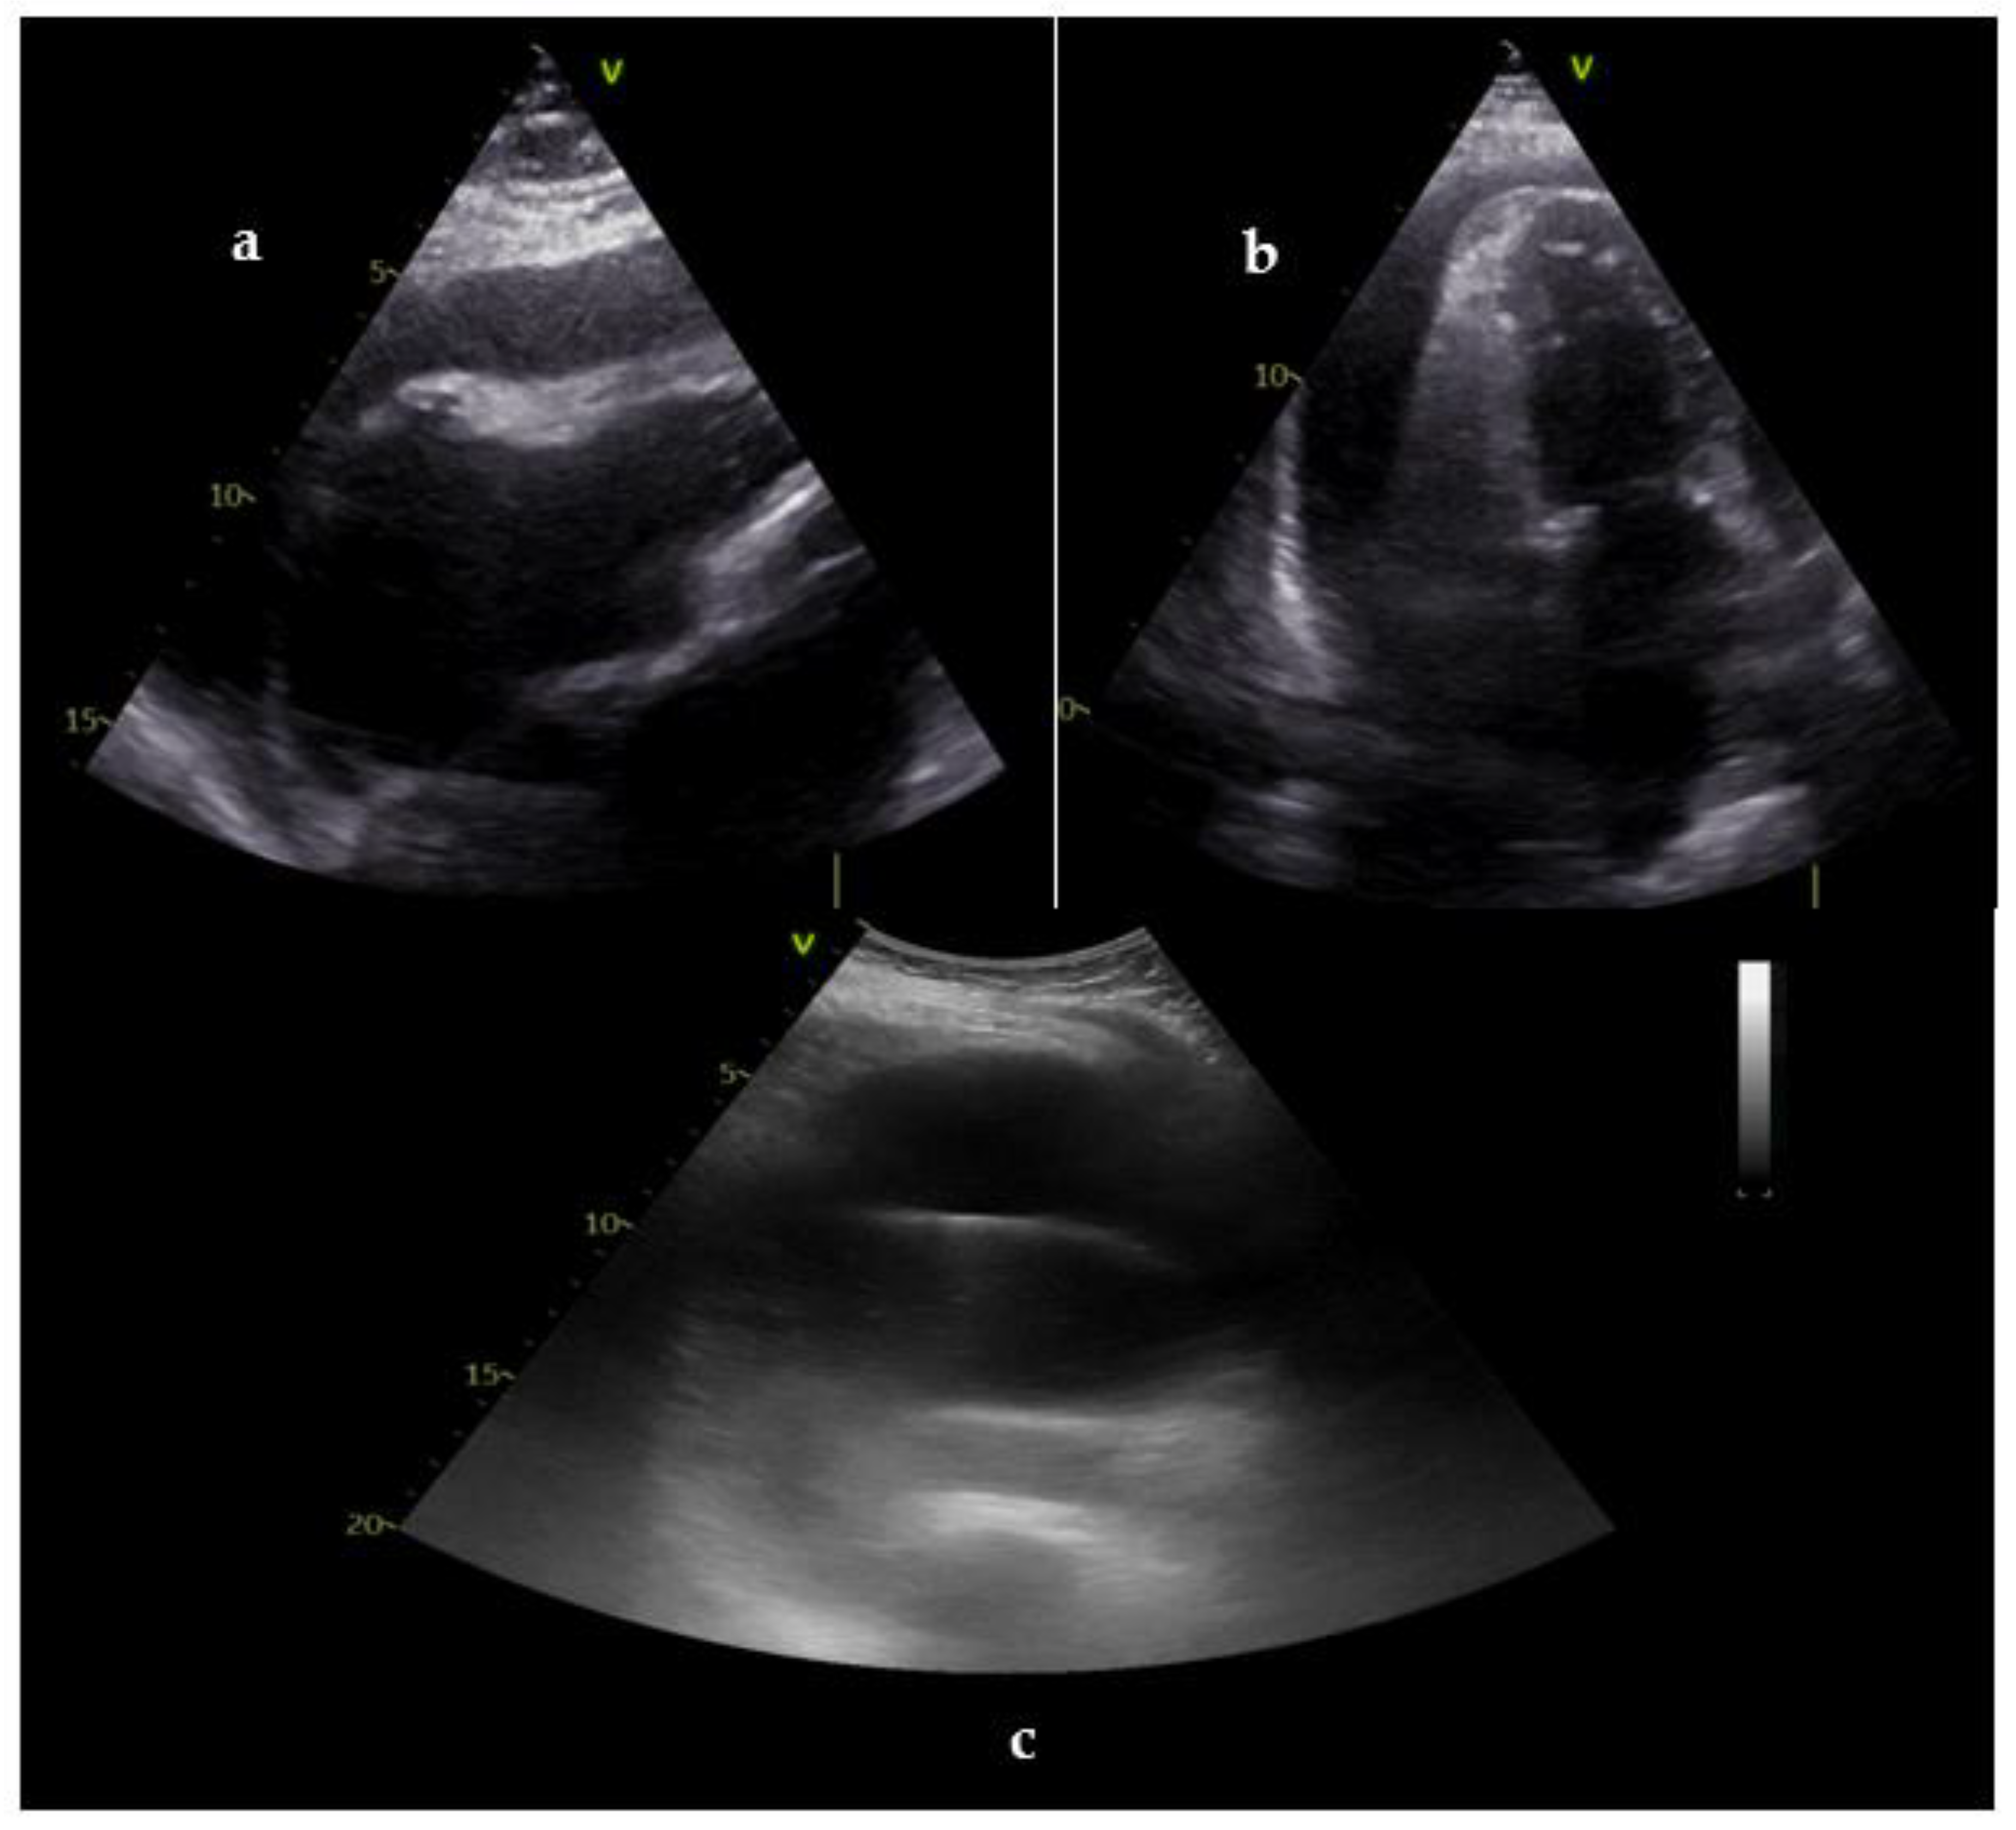

| Potential cause | US views | Suggestive findings | Intervention |

|---|---|---|---|

|

Profound hypovolemia |

Subcostal Abdomen |

Small LV and RV cavity size Near end-systolic obliteration (‘kissing ventricle’) Collapsed IVC (< 10 mm) Massive bleeding in abdomen |

Fluid administration; assess response |

Cardiac tamponade |

Subcostal | Pericardial effusion Collapsed cardiac chambers Congested IVC |

Pericardiocentesis; guide the procedure and assess response |

| Massive pulmonary embolism | Subcostal Lower limbs |

Markedly dilated RV Pressure overload of RV Thrombus-in-transit Congested IVC Presence of DVT (positive CUS) |

Consideration of thrombolysis |

Tension pneumothorax |

Lung | Absence of lung sliding during ventilation | Needle decompression, assess response |